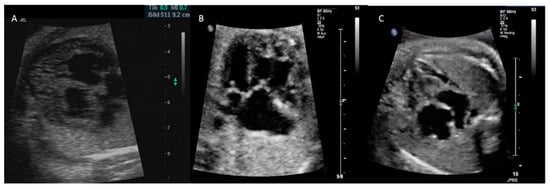

2.3. Ultrasound Assessment

3.1. Prenatal CM Phenotype

4.2. Echocardiographic Evaluation